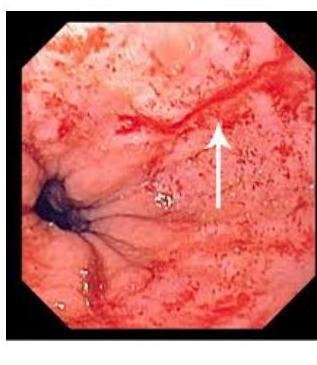

# OTROS TRASTORNOS DEL ESÓFAGO ## * 25-30 cm *LONG TUBE* from *PHARYNX* to the *STOMACH*  ## *FUNCTIONAL* - muscles & nerves - motility of the esophagus ## *MECHANICAL* - something within that blocks the passageway ## * WHAT TYPES OF FOODS PRODUCES THE SYMPTOMS - BOTH *LIQUIDS* & *SOLIDS* - **FUNCTIONAL** - *DYSPHAGIA* FOR ONLY *SOLIDS* - *LUMEN* IS NARROW - *MALIGNANCY* OR *STRICTURE* - CAN BE *INTERMITTENT* or *PROGRESSIVE* # ESPASMO ESOFÁGICO DIFUSO ## DEFINICIÓN Es un trastorno caracterizado por múltiples contracciones espontáneas o inducidas por la deglución, que son de comienzo simultáneo, de gran amplitud, de larga evolución y repetitivas. ## CLÍNICA  - **DOLOR TORÁCICO** (*generalmente retroesternal* y puede tener irradiaciones como cardiopatía) - **DISFAGIA** (*aparece tanto en sólidos y líquidos*, *intermitente* y *no produce pérdida de peso*) ## Edad Media de presentación: alrededor de 40 años. ## DIAGNÓSTICO - El esofagograma con bario y fluoroscopia puede evidenciar el típico **ESÓFAGO EN SACACORCHOS** (**CASCANUECES**) producido por las contracciones anómalas. - La Manometría es el mejor estudio para valorar. Se evidencia **hipertensión del EEI**, el cual se relaja durante las degluciones, a diferencia de la Acalasia.  **UNCOORDINATED HIGH-AMPLITUDE PERISTALTIC CONTRACTIONS**  ## TRATAMIENTO: - Fármacos - *relajantes de fibra muscular lisa* antes de las comidas (**nitroglicerina sublingual**, **dinitrato de isosorbide** y **calcioantagonistas** como **Nifedipino** y **diltiazem**). - **DILATACIÓN CON BALÓN** - **si falla el tratamiento farmacológico**. Dilata la parte inferior del esófago. Ayuda a la **disfagia**. - **Miotomía Longitudinal** - Si fallan los tratamientos anteriores, esta intervención en la capa muscular circular del esófago, junto con una técnica antirreflujo si la presión del *EEI* es baja. # ESÓFAGO ESCLERODERMIA ## DEFINICIÓN Existe una atrofia del músculo liso del esófago con debilidad en la contracción de los dos tercios inferiores del mismo e incompetencia del esfínter esofágico inferior. ## CLÍNICA ## **PRESENTE EN ENFERMEDAD MIXTA DEL TEJIDO CONJUNTIVO.** - Disfagia a sólidos y líquidos. - Disfagia persistente - Estenosis péptica. ## DIAGNÓSTICO - Manometría - Demuestra **disminución amplitud de las contracciones**. - Presión *EEI* basal disminuida, pero normal en deglución. - Endoscopia que evidencia atrofia de músculo. ## TRATAMIENTO - **No puede revertir las anormalidades motoras**. - Se enfoca en **paliar el reflujo y sus complicaciones**.  **HIGH SPECTRUM** **MANOMETRY** ## ANILLO DE SCHATZKI Se forma una banda mucosa delgada y simétrica, localizada en el esófago distal. - Se asocia a **presencia de hernia hiatal y esofagitis eosinofílica**. ## CLÍNICA - **Disfagia intermitente a sólidos**. ## DIAGNÓSTICO ## Esofagograma con bario - Se observa **dilatación en área afectada**.  # Endoscopia - Se observa **membrana delgada**. ## TRATAMIENTO - **Dilatación con balón**. ## DIVERTÍCULO DE ZENKER Son protrusiones de la mucosa faríngea a través de una zona relativamente débil de la pared posterior de la faringe. - Ubicado en la parte superior del músculo cricofaríngeo. - Ocurre con más frecuencia en masculinos ancianos. ## CLÍNICA - Disfagia orofaríngea intermitente. - Halitosis por acumulación de restos. - Regurgitación. - Aspiración pulmonar. - Puede ser palpado a la EF. ## DIAGNÓSTICO - Esofagograma con Bario. - Se observa el divertículo. - **NO ENDOSCOPIA POR RIESGO DE PERFORACIÓN**. ## TRATAMIENTO - **Corrección quirúrgica**.  # PÓLIPO ESOFÁGICO ## DEFINICIÓN Los pólipos fibrovasculares del esófago son tumores benignos raros, caracterizados por el desarrollo intraluminal de una masa pedunculada de localización principal en el esófago cervical a nivel cricofaríngeo, no produce molestias por largo tiempo, sin embargo, puede ocurrir la regurgitación del pólipo, produciendo asfixia o **más FRECUENTEMENTE DISFAGIA**. ## CLÍNICA A pesar de su gran tamaño y potencial crecimiento, la transformación maligna es bastante rara. Usualmente crecen en el tercio proximal y permanecen asintomáticos por largo tiempo. Cuando son sintomáticos, el cuadro clínico puede ser espectacular y a veces letal por **obstrucción de la vía aérea**. ## DIAGNÓSTICO Puede ser por tomografía computarizada y resonancia magnética cuando se analiza mediastino. La endoscopía permite una visualización directa y fácil para su diagnóstico y valoración. ## TRATAMIENTO Depende del tamaño del tumor; así, los pólipos menores de 2 cm pueden ser extirpados por endoscopía, sin embargo, en la mayoría de los casos, se requiere de la **escisión quirúrgica**.  # SÍNDROME DE MALLORY-WEISS Consiste en **hemorragia digestiva alta** que se produce como consecuencia de erosiones longitudinales en la región de la unión gastroesofágica. ## **RESULTADO DE INTENSOS VÓMITOS O INCLUSO TOS.** - Las lesiones se ubican en el lado gástrico de la unión gastroesofágica. - El sangrado cesa en el 80-90% espontáneamente. ## DIAGNÓSTICO **Endoscopia** (la cual puede ser terapéutica) ## TRATAMIENTO - **Embolización**. - Casos raros **cirugía**.  ## SÍNDROME DE BOERHAAVE Se trata de la rotura de la pared esofágica a consecuencia de vómitos de repetición. Provoca mediastinitis y complicaciones de la misma. ## ETIOPATOGENIA 1. **Aumento repentino de la presión interna del esófago** producida durante los vómitos intensos. 2. Consecuencia de una **falta de coordinación neuromuscular** que causa un fallo del cierre del músculo cricofaríngeo (el esfínter inferior del esófago). ## CLÍNICA - **Dolor retroesternal** (Mediastinitis)  ## DIAGNÓSTICO **ESOFAGOGRAMA**: se confirma hasta en 90% de los casos por la observación de extravasación de medio de contraste en el esofagograma. ## TRATAMIENTO - Antibióticos. - Reparación quirúrgica. **UBICACIÓN HABITUAL - PARED POSTERIOR DE LOS 2/3 INFERIORES DEL ESÓFAGO 2-3cm ANTES DEL ESTÓMAGO**